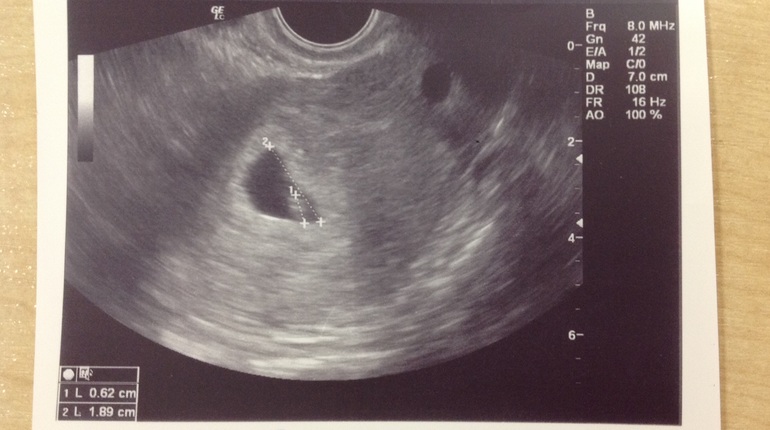

До этого успели заскочить на УЗИ!!! Безумно рада, что вдвоем! И так спонтанно, позвонили будучи в дороге и приехали, благо записи не было! Повезло нам!

Слушали наше маленькое сердечко) как у кролика))) смеюсь, быстро так стучит.

Доктор снова с меня порадовалась, первым моим вопросом было, эмммм, значит новый человек это вот это серое пятно?!)))

А если серьезно, это непередаваемо!! Ты слышишь это бум-бум и отчетливо понимаешь, что внутри тебя новая жизнь! Новый человек и он живой! Это так непостижимо! До слез! Я безумно люблю свое пянышко, моего родного человечка!